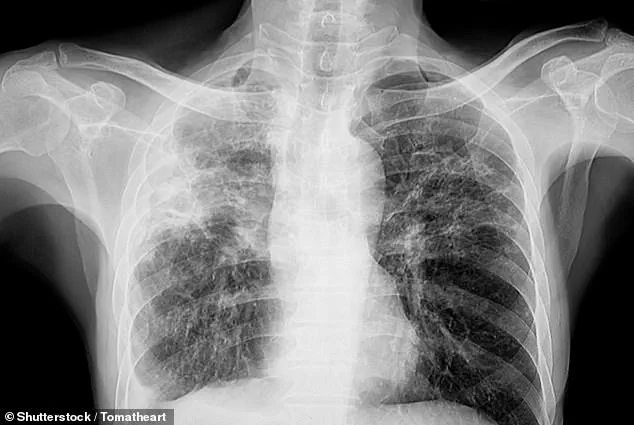

This silent threat is linked to a chronic lung disease called pulmonary fibrosis, which affects more than 70,000 Britons.

The condition causes scarring of lung tissue, making breathing difficult and reducing oxygen levels in the blood.